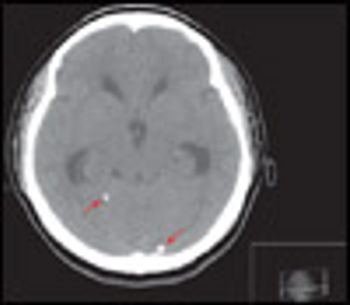

An 18-year-old woman from Mexico was hospitalized because of severe headache with nausea and vomiting. Her headaches had started 4 years earlier and had progressively worsened. They occurred mainly in the occipital region and were pulsating, worse on bending down, and unrelieved by any medication. They were often accompanied by dizziness and presyncope.